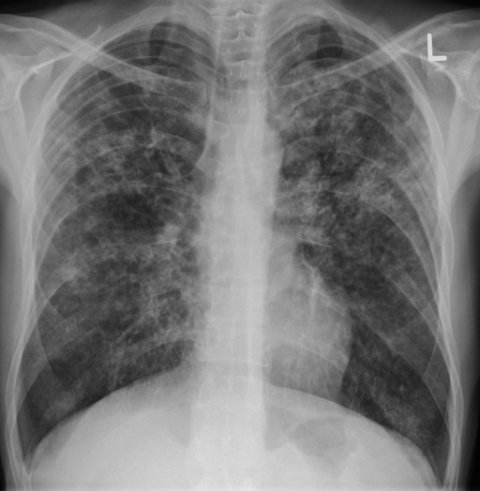

A patient with TB credit James Heilman, MD

TB is an infectious disease usually caused by the bacteria Mycobacterium tuberculosis. Despite being completely curable, TB is the second leading cause of death from an infectious disease after COVID-19. TB mainly affects the lungs, but is known to affect other parts of the body such as the abdomen, glands, bones, and nervous system.